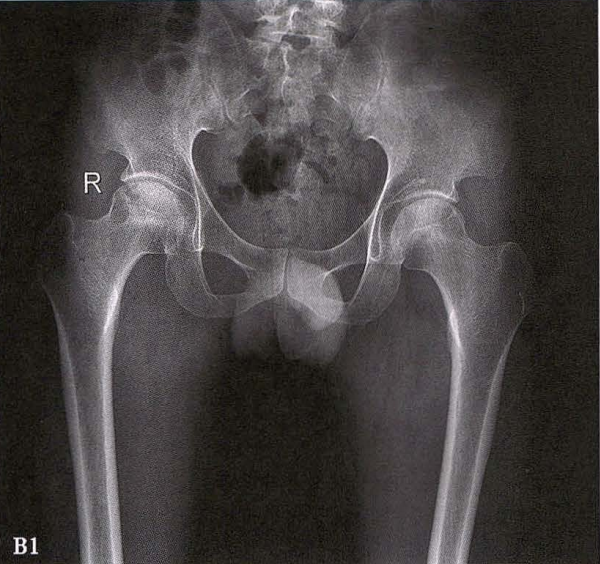

B.男性,31岁,双侧股骨头坏死,双侧均为Ⅲ期。X线片示双侧股骨头密度不均、股骨头稍变扁(B1)。MRI(T1加权像)示股骨头内多发不规则信号带(B2),股骨头内凸向大转子的双线征(白色箭)和软骨下骨骨折(白色三角)。